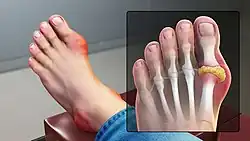

La fluxion goutteuse se présente par une douleur soudaine et vive et par le gonflement d'une articulation. Elle n'atteint en général qu'une articulation par crise et d'abord les orteils, en particulier la base du gros orteil, avec l'articulation métatarso-phalangienne[18] (on parle de « podagre », ce qui signifie « pris par le pied dans un piège », soulignant pour les anciens l'intensité de la douleur) mais aussi parfois les chevilles, les talons, les genoux et, beaucoup plus tardivement, les articulations des doigts et les poignets. Cette douleur, qui se déclenche souvent la nuit, est insomniante et empêche tout contact avec l'articulation (même avec les draps du lit). Le pic d'intensité douloureuse est atteint en moins d'une journée et la crise se résout spontanément en une à deux semaines[19]. Sans traitement, elles se répètent avec des intervalles libres de plus en plus courts.

- Inflammation douloureuse au niveau de l'articulation métatarso-phalangienne du gros orteil